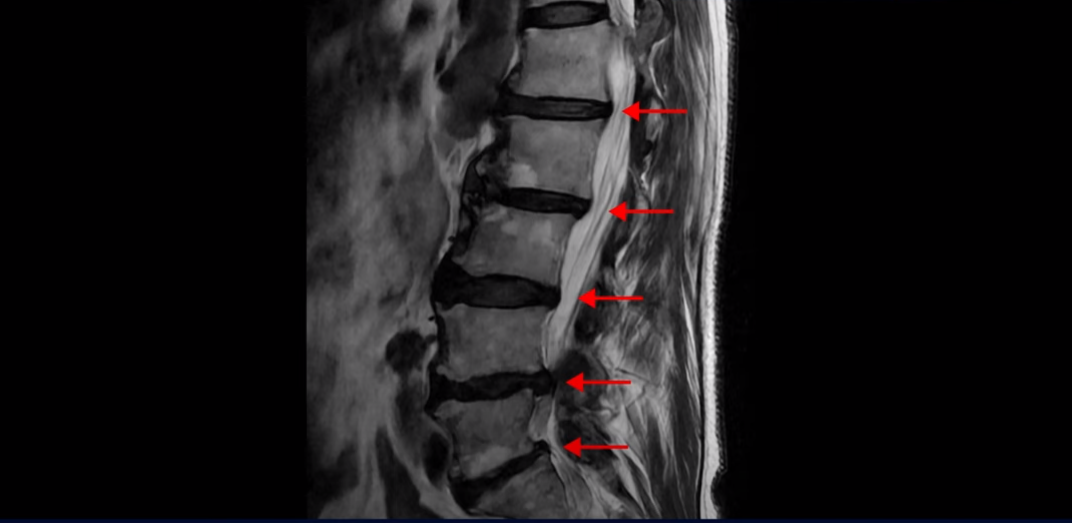

협착증은 노화 때문에 생기는 질환입니다. 나이가 들수록 노화와 퇴행 때문에 신경 구멍이 조금씩 좁아집니다. 이분도 신경 구멍이 좁아져 있습니다. 보시다시피 척추 여러 마디가 퇴행되어 있고

특히 왼쪽 신경가지가 빠져나가는 추간공들이 많이 좁아져 있습니다.

이분은 약 한달 전에 갑자기 왼쪽 다리를 아예 못 쓸 만큼 심하게 아프게 되었는데 허리를 펼 수도 없고 몇 미터 걸을 수도 없는 상태였습니다. 신경 주사를 여러 대 맞아도 전혀 듣지 않는 상태였는데 이분처럼 MRI 검사에서 신경구멍이 좁아져 있고 신경주사가 아예 듣지 않으면 십중팔구 수술하자는 얘기를 듣게 됩니다.